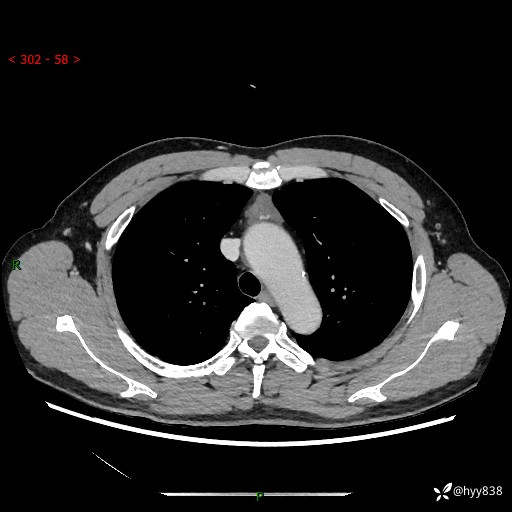

患者性别:女

患者年龄:49岁

简要病史:跟骨骨折,常规CT发现纵隔占位

辅助检查:CT

临床诊断:纵隔占位

增强(动脉期+静脉期)